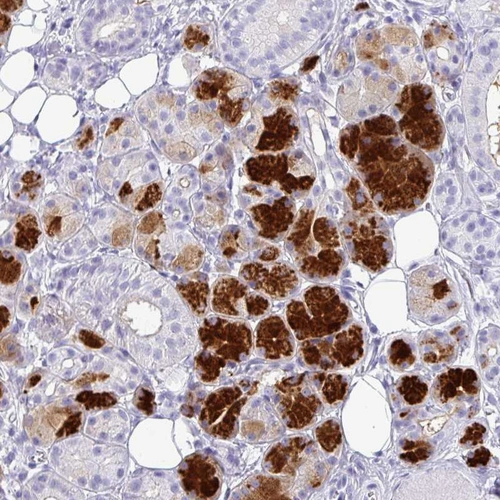

Immunohistochemistry analysis in human salivary gland and liver tissues using HPA046980 antibody. Corresponding AMY1A RNA-seq data are presented for the same tissues.